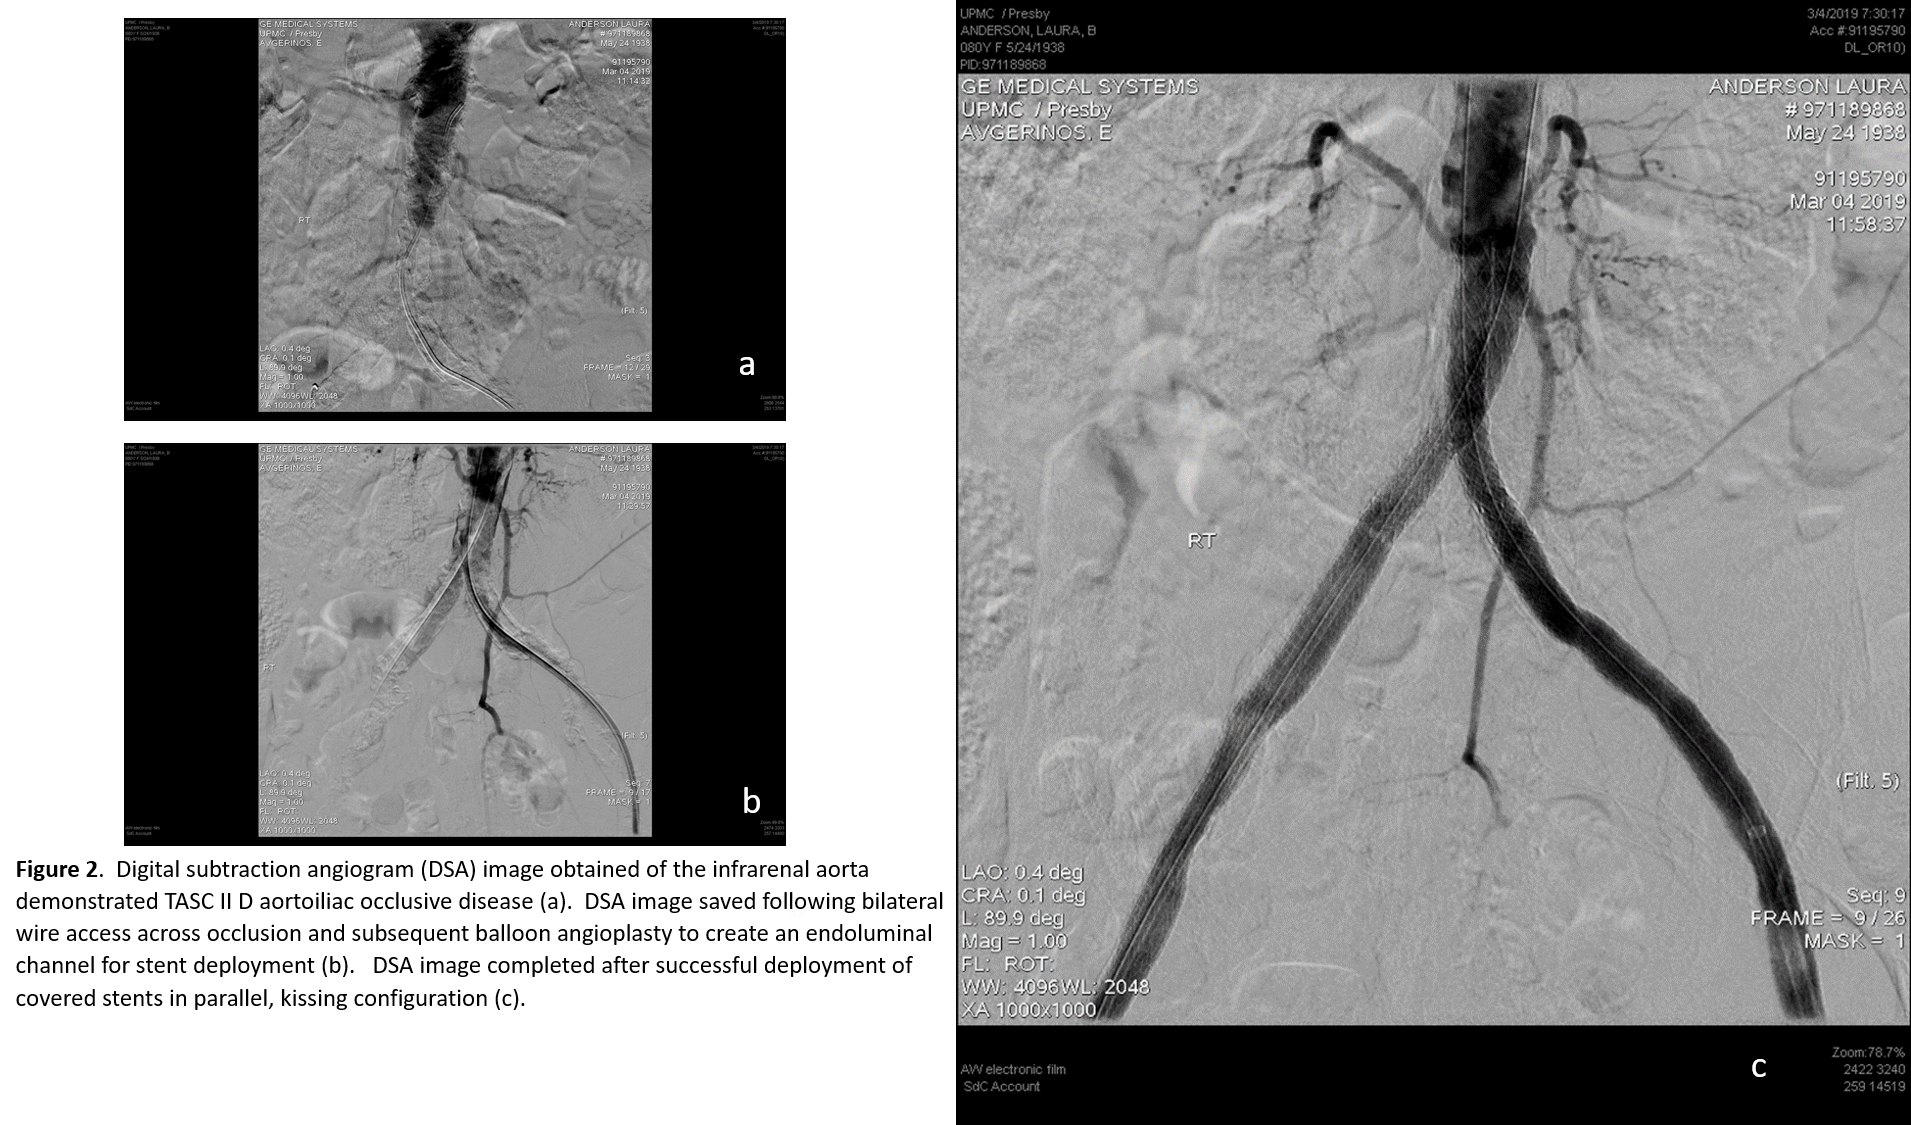

An 80-year-old female was transferred to UPMC Presbyterian from an outside hospital with rest pain, tissue loss, and a mid-aortic and bilateral common iliac artery occlusion (Figure 1a). She had severe three-vessel coronary disease on recent cardiac catheterization. A hybrid procedure was performed via percutaneous, ultrasound-guided access of right common femoral artery and a left femoral exposure to perform an endarterectomy with profundaplasty given its severe atherosclerotic burden (Figure 1b). The chronic thrombotic occlusions of the iliac arteries and aorta were crossed bilaterally, pre-dilated, and stented. Bilateral balloon-expandable stents were deployed simultaneously in the mid-infrarenal aorta in a parallel kissing stent configuration (Figures 2 a-d), and covered self-expanding stents were utilized for the bilateral external iliac disease. She was discharged home with family a few days following the procedure with resolution of her rest pain.